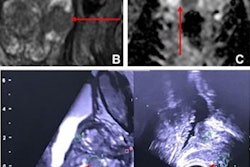

Axial T1-and T2-weighted (T1w and T2w, respectively) MRIs of infants and young children with normal myelin maturation at the level of corpus callosum and lateral ventricles. Note that the images are resized to keep the focus only on progression of myelin maturation at different months. (A) A term newborn with meconium aspiration syndrome who underwent imaging to rule out ischemia, infarction, or hemorrhage. (B) A 6-month-old infant with a history of asphyxia and sinus vein thrombosis at birth but with normal development. (C) A 12-month-old child with an ocular hemangioma who underwent imaging to rule out intracranial pathology. (D) A 24-month-old child with headache for 2 months. (E) A 36-month-old child with a history of focal seizures, imaging is performed to rule out structural changes. Images and caption courtesy of the RSNA.The group tested the three models on an internal dataset and on two external sets (these external sets included information from the National Institutes of Health pediatric brain MRI database and the Developing Human Connectome Project database). The team then evaluated the models' performance for assessing myelin age in months using mean absolute error (MAE) and Pearson correlation coefficients.